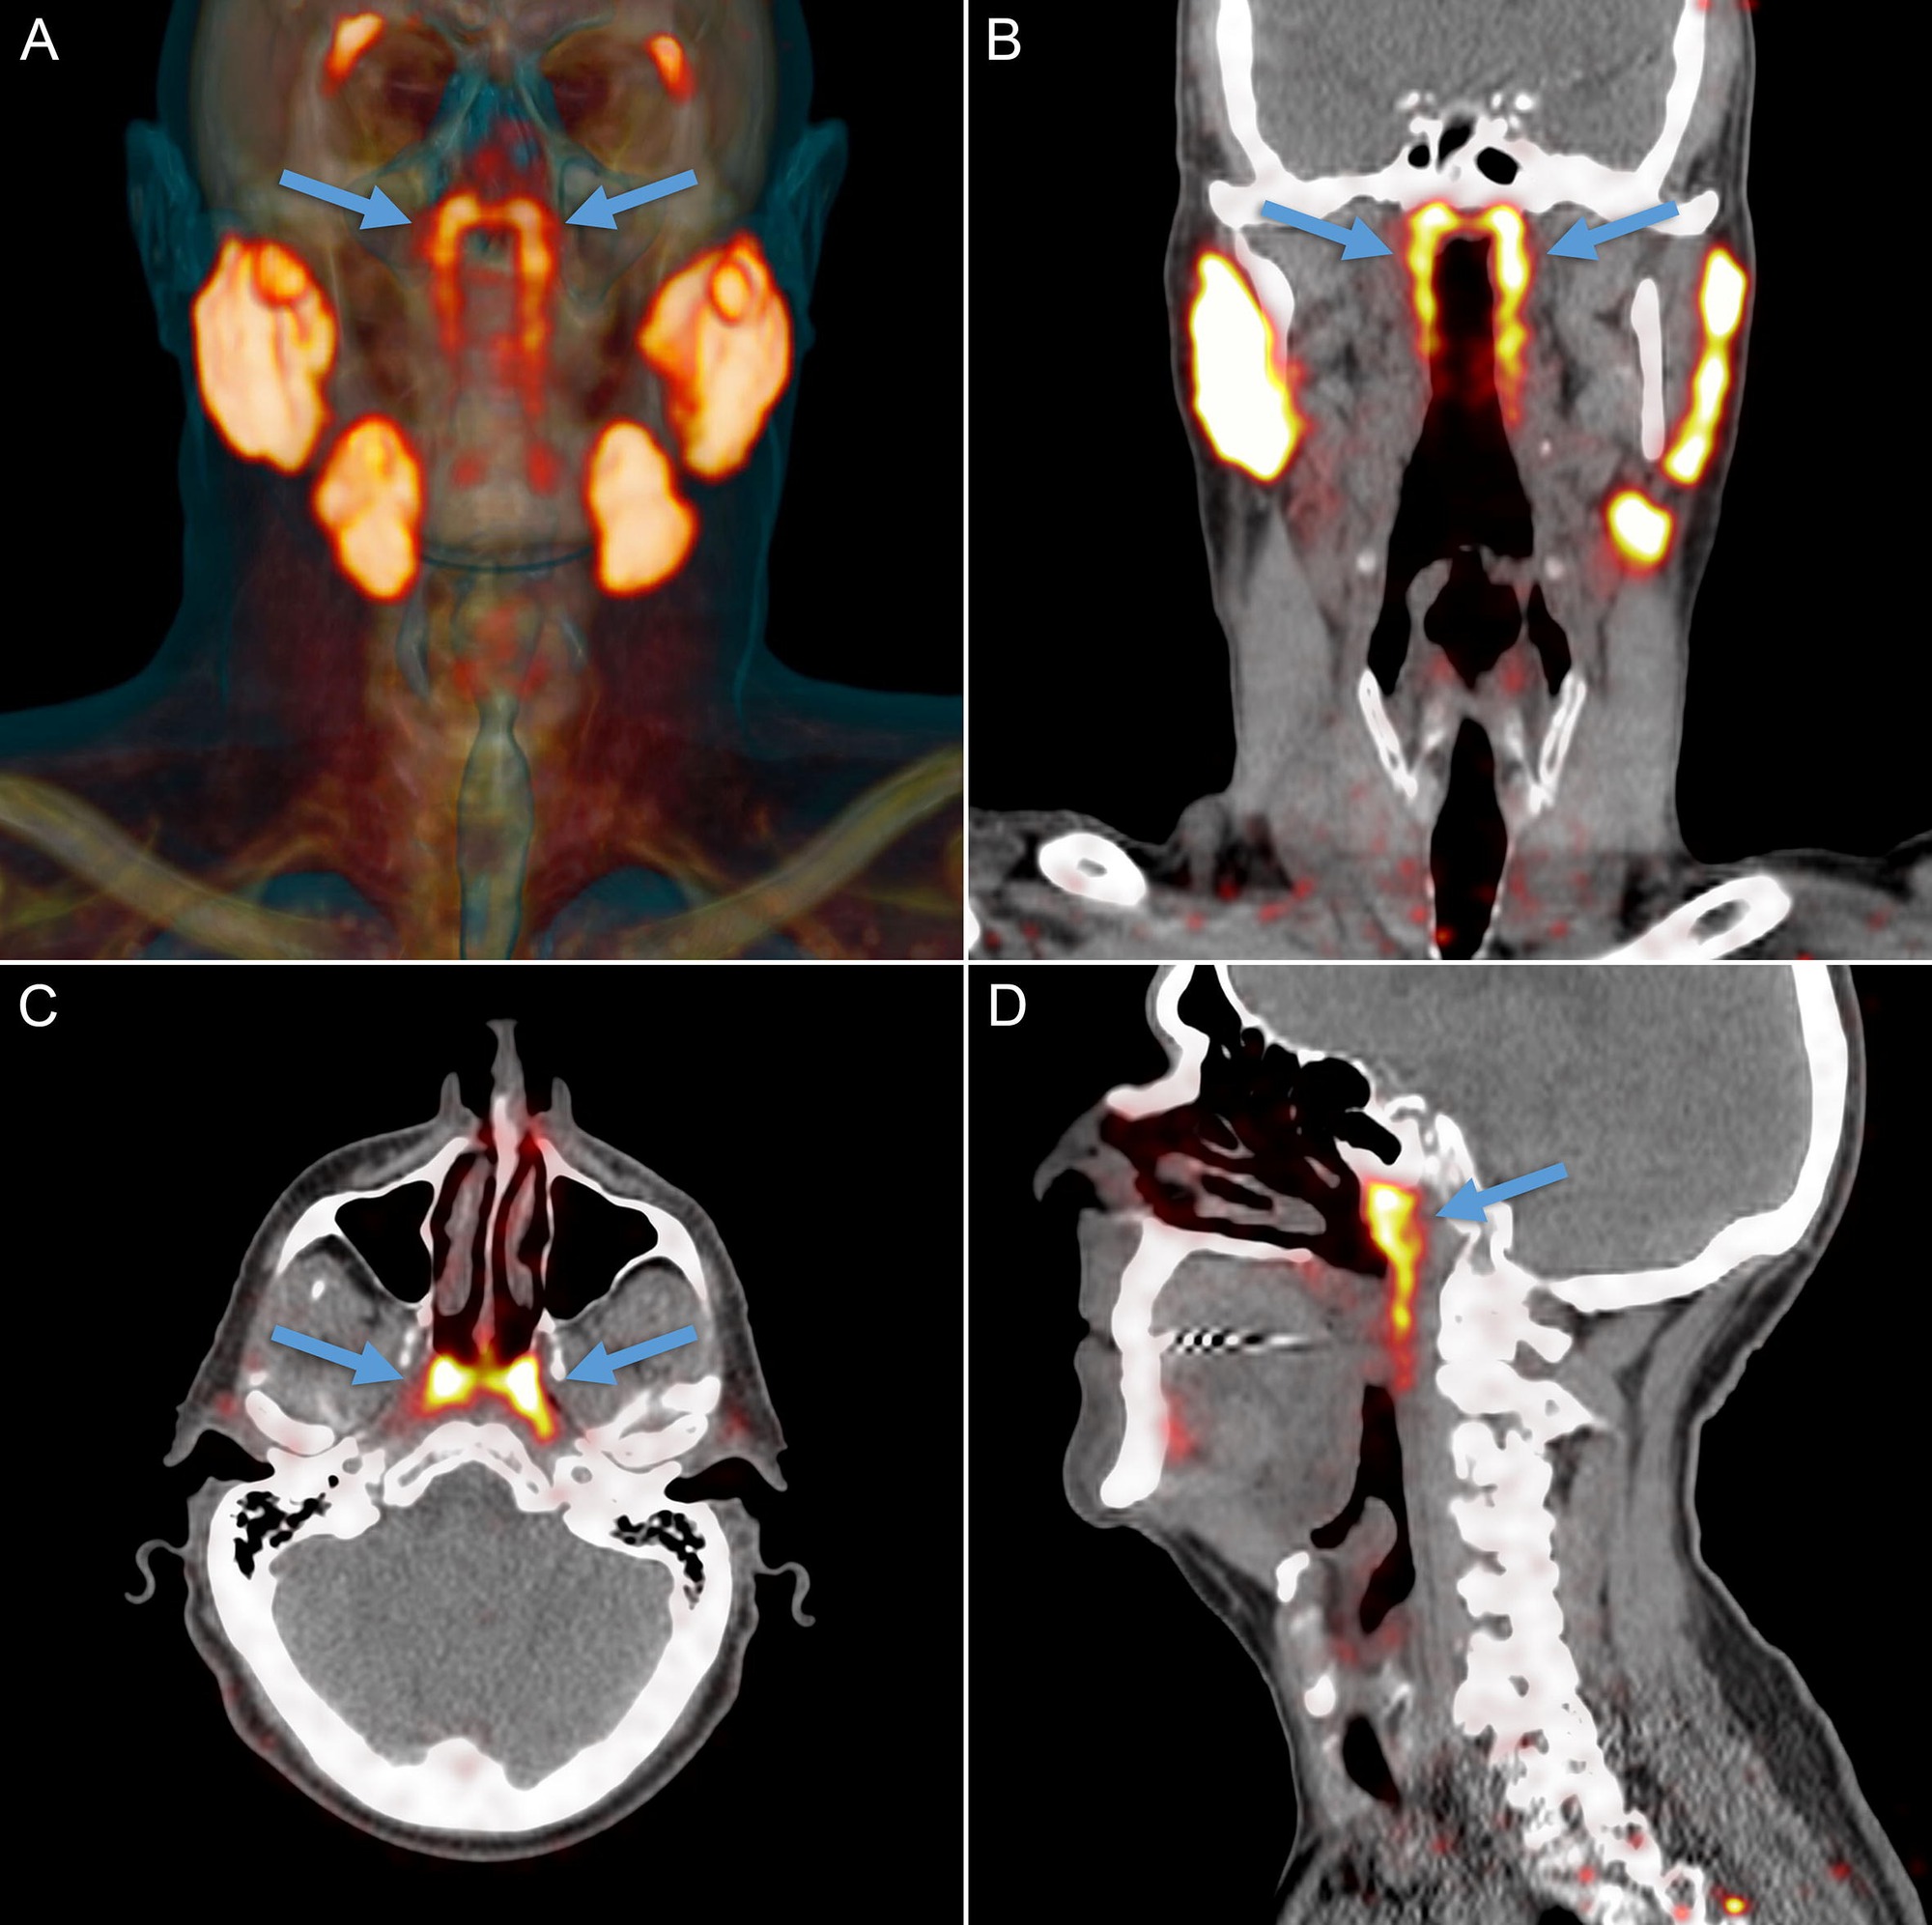

Phát hiện có chiều hướng mang ý nghĩa lâm sàng rõ rệt: nếu tuyến này thực sự tồn tại và đóng góp vào việc giữ ẩm, bôi trơn vòm họng, thì trong xạ trị vùng đầu-cổ các bác sĩ cần tránh bắn quá mạnh vào khu vực này. Bằng chứng sơ bộ từ nhóm nghiên cứu cho thấy bệnh nhân chịu liều xạ cao ở vùng này thường gặp khô miệng, khó nuốt là những di chứng ảnh hưởng nghiêm trọng đến chất lượng sống. Vì vậy, "phát hiện tổn thương có thể tránh được" này được mô tả như một cơ hội để giảm tác dụng phụ của điều trị ung thư.

Nếu tuyến này thực sự tồn tại và đóng góp vào việc giữ ẩm, bôi trơn vòm họng, thì trong xạ trị vùng đầu-cổ các bác sĩ cần tránh bắn quá mạnh vào khu vực này. (Ảnh: The Scientist)

Kể từ đó, một số nghiên cứu độc lập đã vào cuộc kiểm chứng. Một nghiên cứu miễn dịch mô học công bố năm 2023 đã phân tích mô và kết luận các đặc điểm mô học của tuyến nước bọt ống hầu giống nhiều nhất với tuyến nhỏ ở vòm khẩu cái (palatal salivary glands) và điều này củng cố quan điểm: đây là mô tuyến thật sự, có cấu trúc ống và tế bào biểu mô đặc trưng của tuyến nước bọt.

Tuy nhiên, các nhóm khác lại chỉ ra rằng đóng góp chức năng của tuyến này vào tổng thể nước bọt là nhỏ, và vì thế ý nghĩa lâm sàng (ví dụ: mức độ gây khô miệng khi bị xạ) có thể bị phóng đại.